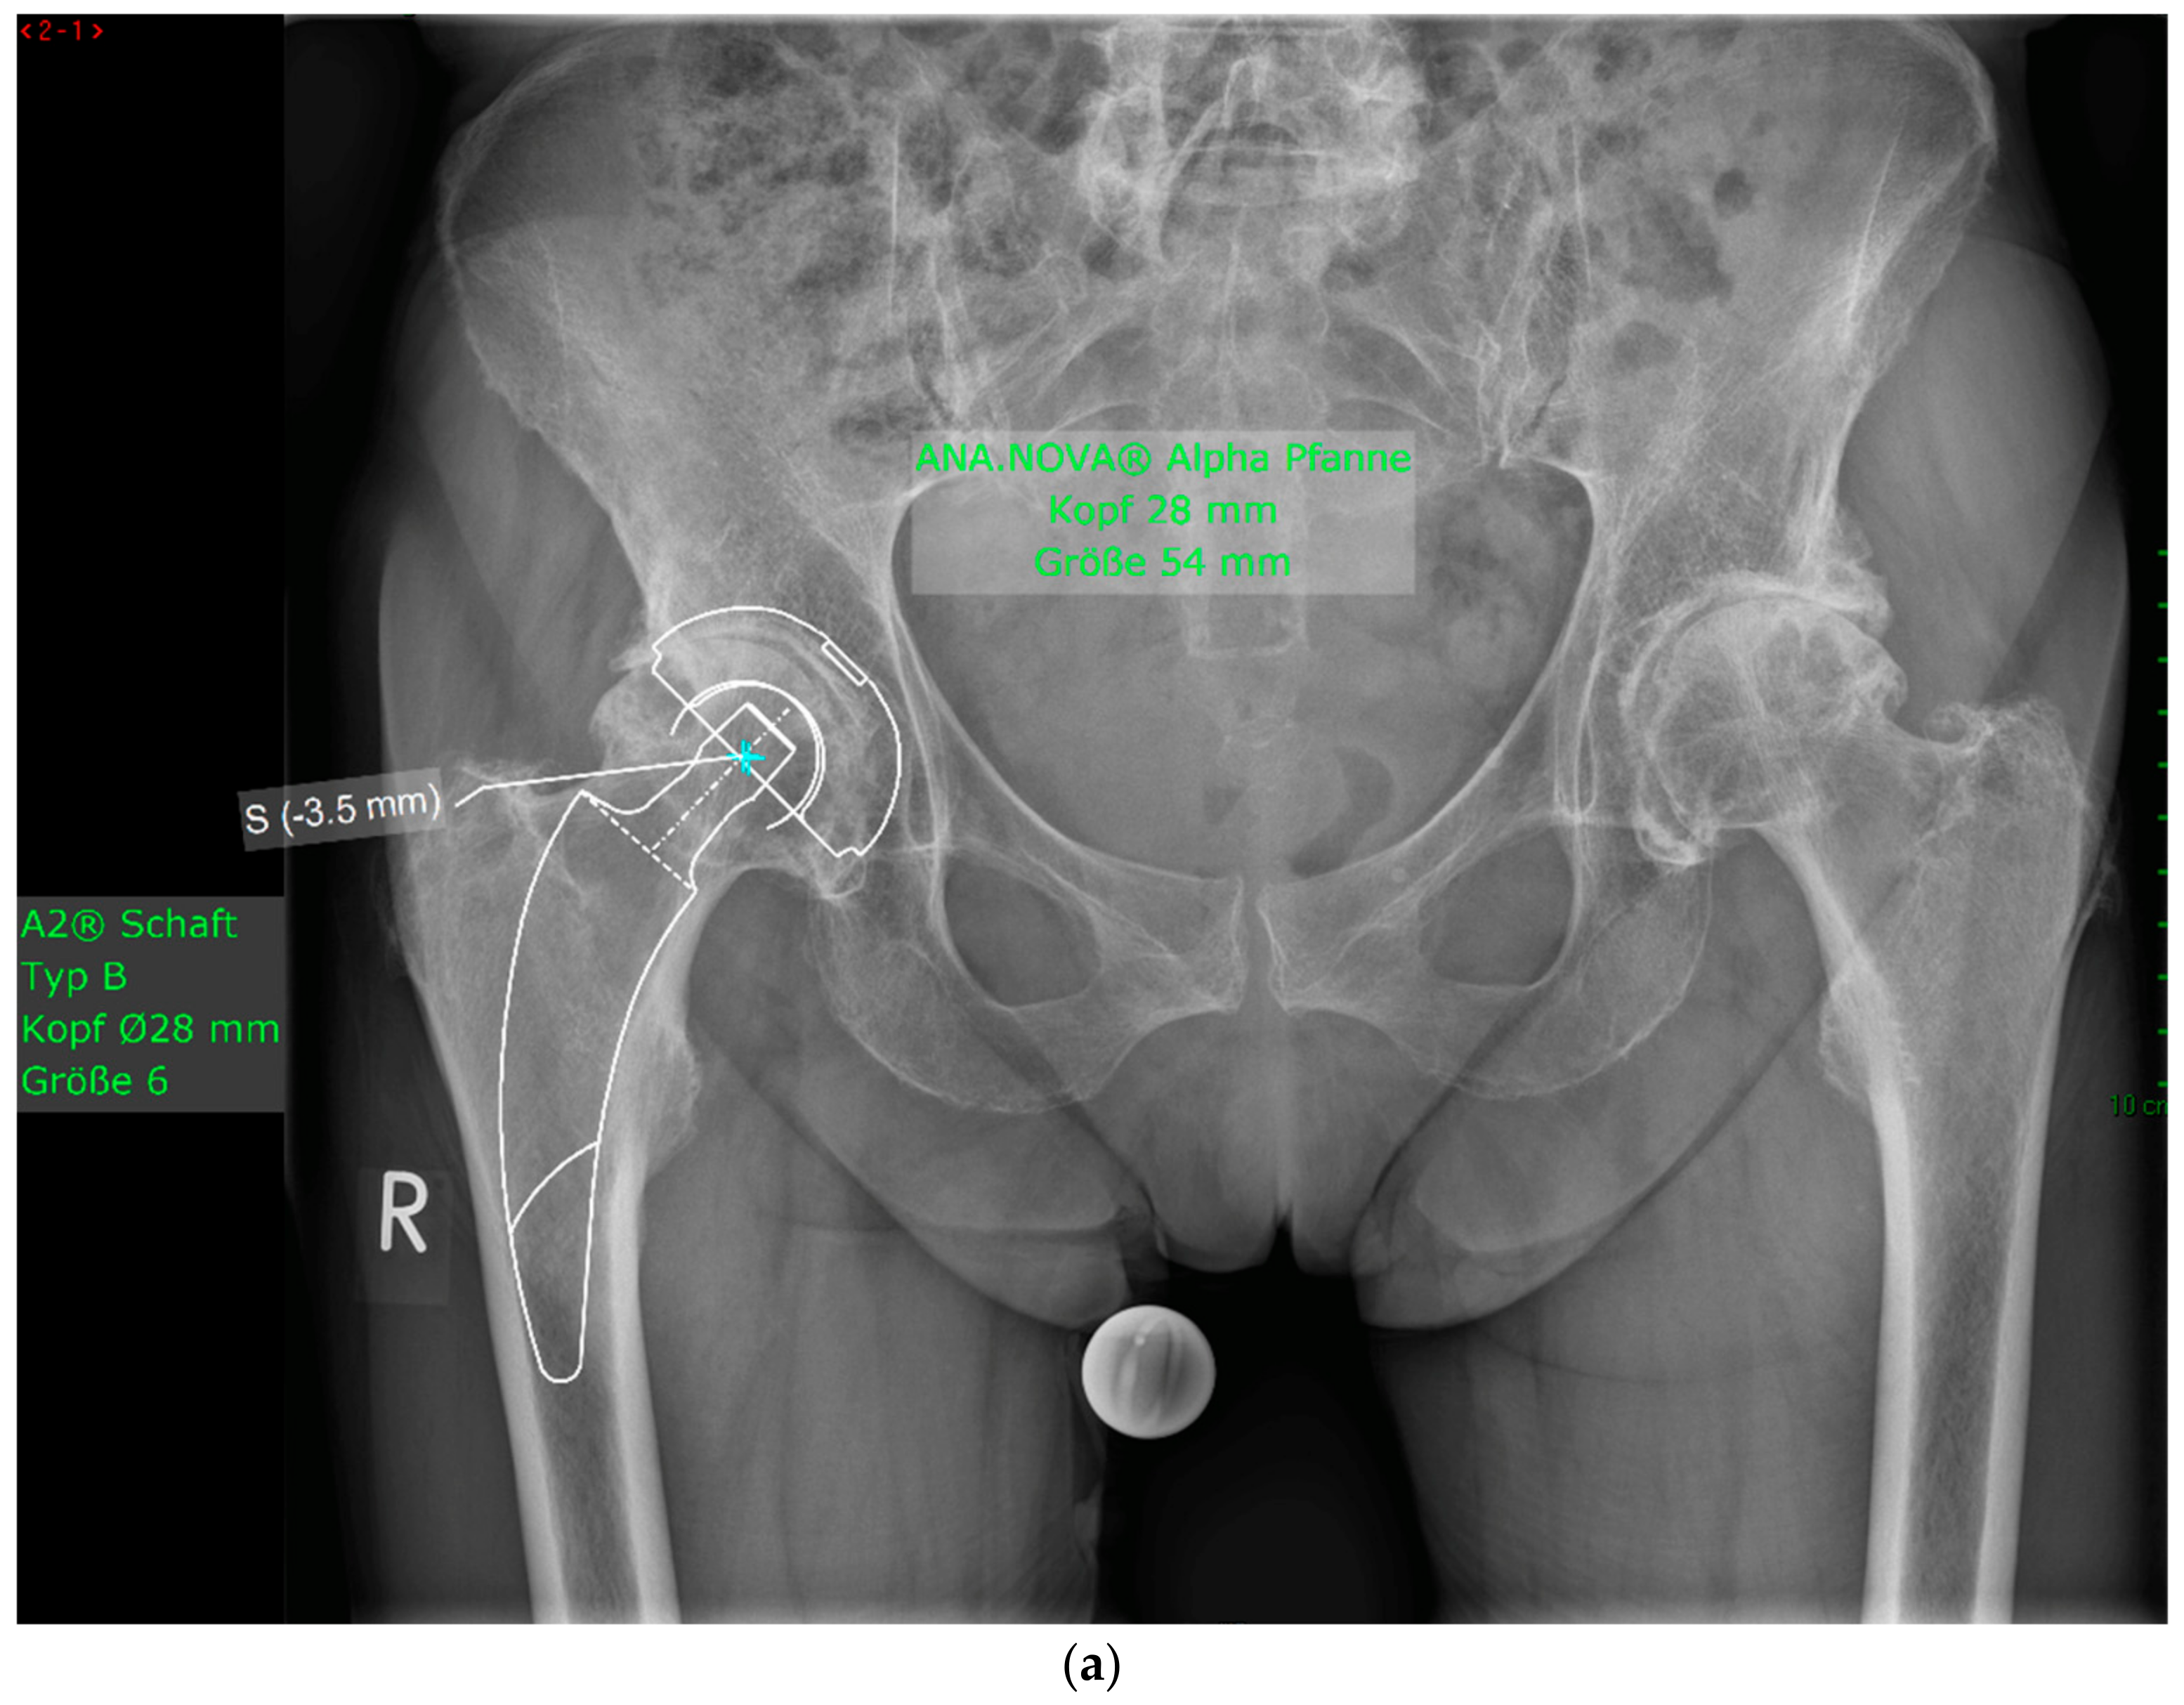

Figure 4.

(a) Case #3: Osteoarthritis, female, 81 years old, preoperative planning. (b) Correct implant position 1 week postoperatively. Homogeneous cement mantle.